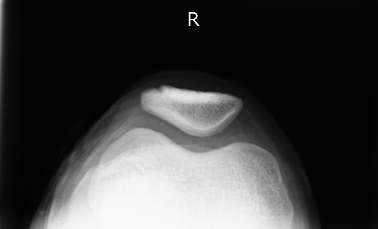

単純X線写真

X線:分裂片の辺縁が平滑・皮質化していれば古くからの癒合不全を示唆。

骨折との鑑別:骨折は鋭い不整縁、周囲骨髄浮腫(MRI)、外傷歴が手掛かり。